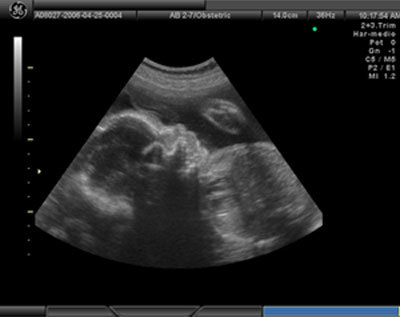

La ecografía es una técnica que utiliza ondas de ultrasonido que se reflejan en los diferentes tejidos del cuerpo humano, y al volver al transductor, se transforman en señales que permiten ver imágenes de estos tejidos en una pantalla.

Como es sencilla, inocua y barata es la técnica que más se utiliza dentro de las pruebas prenatales para el seguimiento del embarazo. Para realizarla, el médico desliza un dispositivo llamado transductor sobre la tripa de la embarazada o lo introduce por la vagina, según lo avanzada que se encuentre la gestación.

• Entre la 8-14 semana: se realiza transvaginal. La principal utilidad es calcular la edad gestacional midiendo la longitud cráneo-raquídea (CRL). También descarta embarazo ectópico, embarazo múltiple y malformaciones (valora entre otras cosas el pliegue nucal, osificación hueso nasal, dopler del ductus arterioso) Ya se puede sentir el latido del corazón del bebé (apartir de 7ª semana).

• Entre las 18-20 semanas : por medio trans-abdominal. Sobre todo para la valoración de posibles malformaciones, y seguimiento de la edad gestacional por medio de la medición del diámetro biparietal (DBP), longitud del fémur y diámetro abdominal.

• Entre las 34-36 semanas: trans-abdominal, descarta un posible retraso de crecimiento del bebé intraútero

La realización de esta prueba durante el segundo y el tercer trimestre es lo más eficaz para estimar la edad gestacional. Esto se consigue midiendo el diámetro entre los huesos parietales del cráneo y la longitud del fémur. Tenemos que tener en cuenta que a medida que el embarazao progresa, se hace más difícil calcularlo con la ecografía, pudiendo ser en el último trimestre con una variación de +/- 21 días.